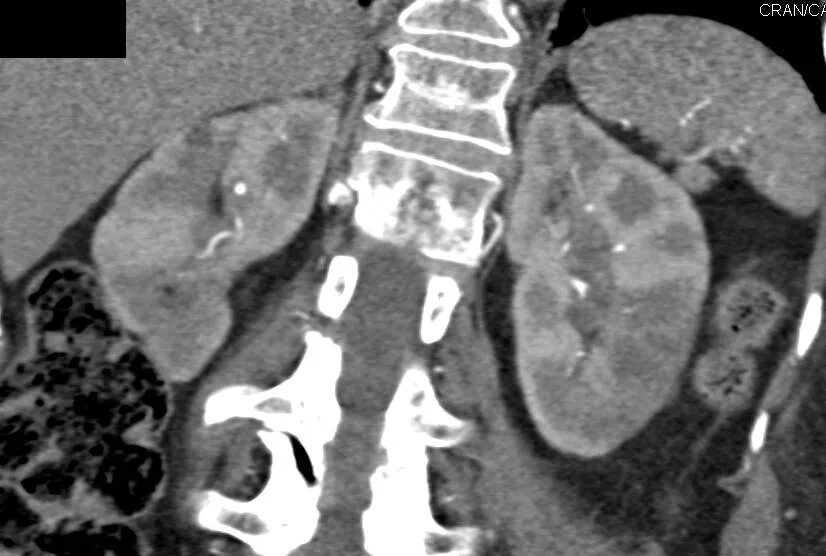

Пиелонефрит кт